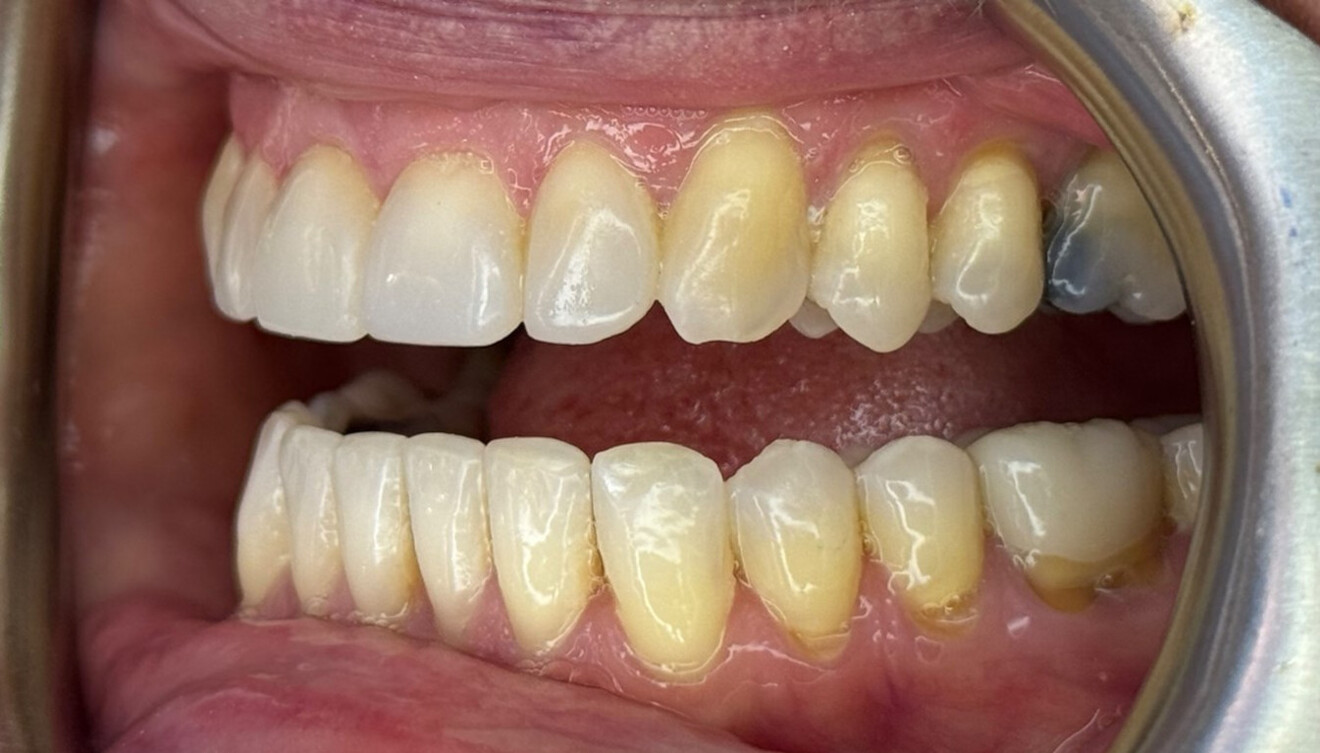

Figs. 6a–e: Intra-oral post-treatment photographs.